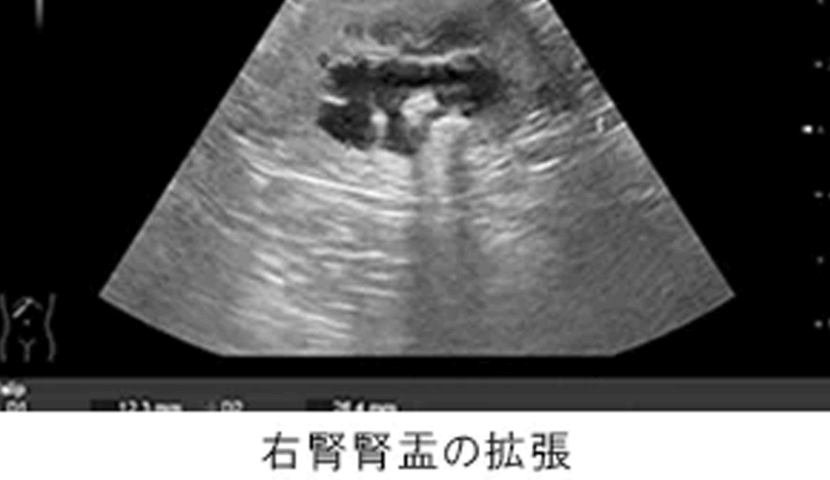

血液検査で腎数値の上昇、超音波検査で左腎の萎縮、右腎腎盂の顕著な拡張、右尿管内の結石を確認。

左腎は慢性腎不全の進行による萎縮、右腎は結石の尿管閉塞による腎盂拡張及びそれに伴う急性腎不全と診断。左腎の機能は著しく低下していると判断し、右腎の機能をより確実に確保するために比較的新しい治療法であるSUBシステム手術を実施。